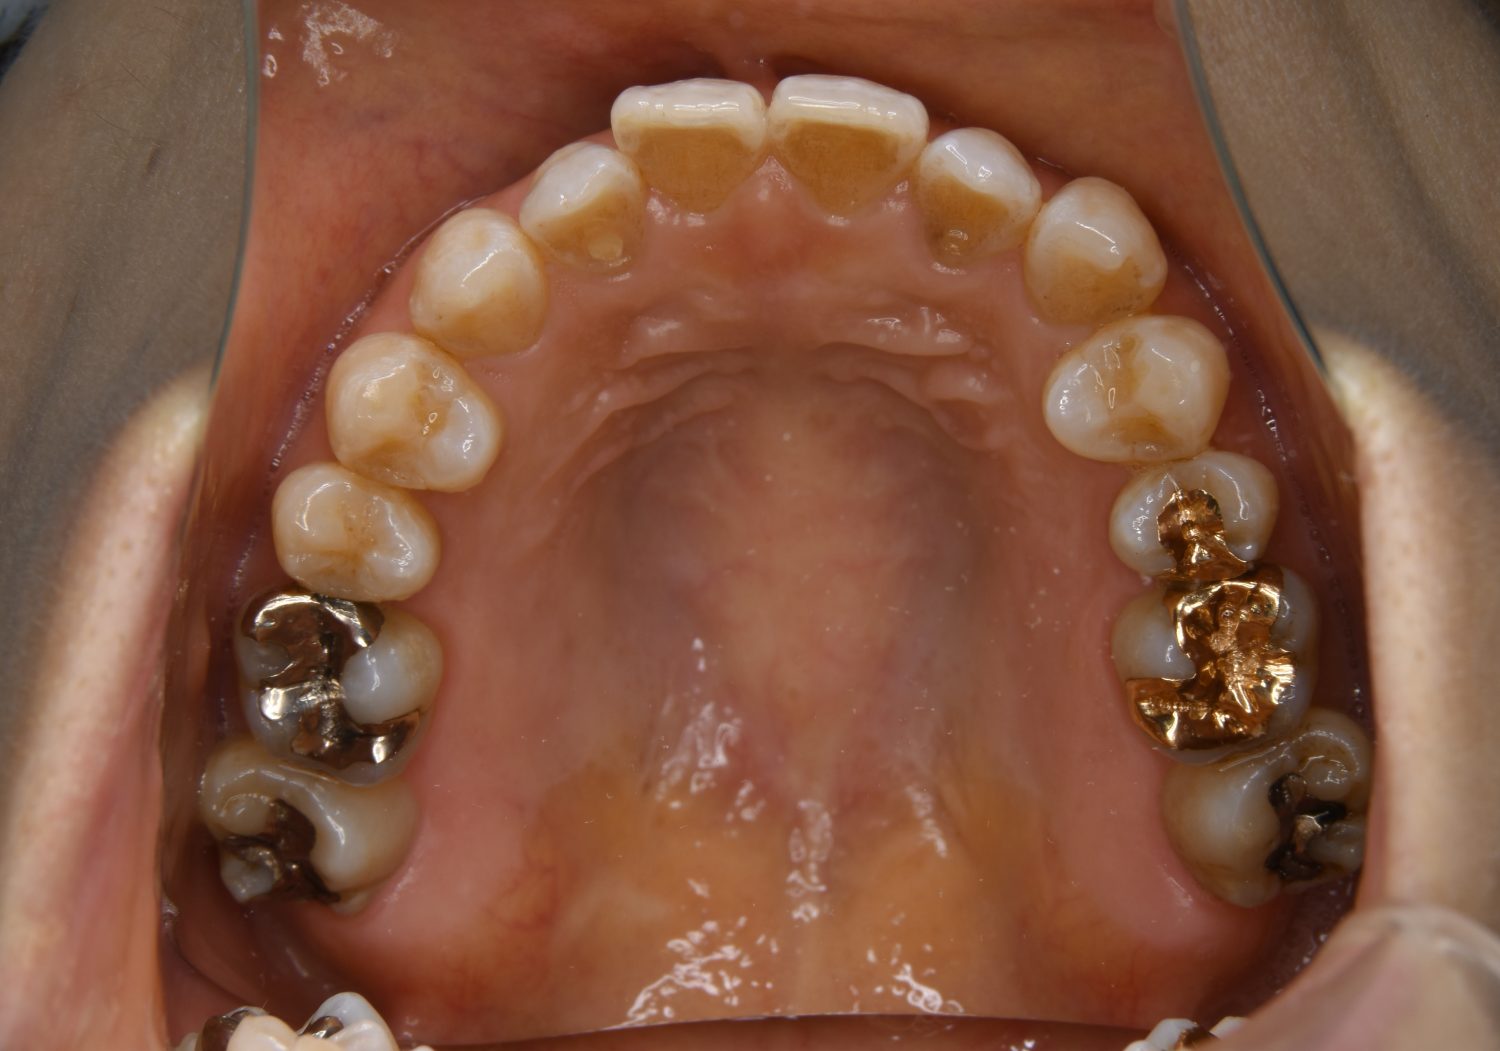

Before

主訴

前歯で物が噛めない

治療内容

上下ラビアルブラケット(唇側装置)に矯正用アンカースクリューを併用し非抜歯で治療を行いました。

治療費

1,000,000 円(税込)

治療期間

26ヶ月

通院回数

27回

想定されたリスク

※歯根吸収、歯肉退縮、歯髄壊死、顎関節症状

上下の前歯が開いており前歯では全く噛めていない状態でした。臼歯の圧下を行うことで機能面のみでなく審美面も改善しました。